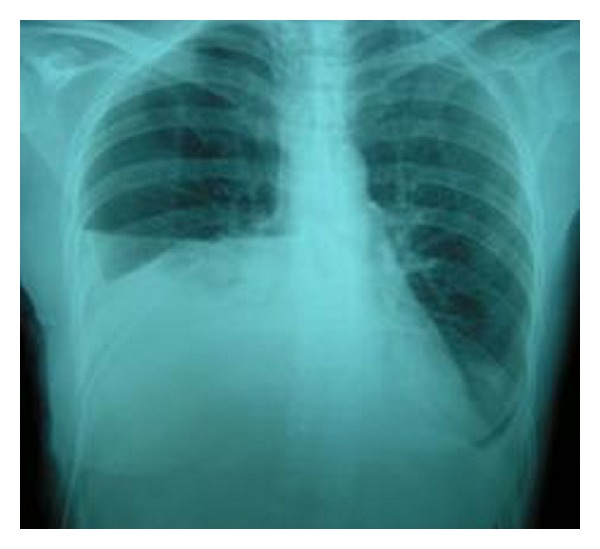

A 45-year-old woman was referred to our department with complaints of high-grade fever and progressive shortness of breath. The patient had undergone diagnostic right ureteroscopy for recurrent renal colic at a different centre one week ago. She had a history of gastrectomy due to gastric carcinoma three years earlier, with subsequent chemotherapy and irradiation. There was no past history of pulmonary or heart disease. On clinical examination, the patient was febrile with a high respiratory rate. Chest radiograph showed massive pleural effusion on the right side (Figure 1) and chest CT (computed tomography) confirmed the diagnosis revealing bilateral pleural effusion (Figure 2). The patient was emergently managed with right closed pleural drainage. Biochemical evaluation of the drainage fluid indicated that it was urine. IVU (intravenous urography) and abdominal CT demonstrated retroperitoneal urine accumulation. This was a possible iatrogenic complication during the previous ureteroscopy. After the subsiding of the respiratory symptoms this urine collection was further treated with percutaneous nephrostomy and drainage of the retroperitoneal space. The chest tube was removed on the fourth day without recurrent effusion.

Figure 1.

Case 1: chest radiograph showing pleural effusion on the right side.